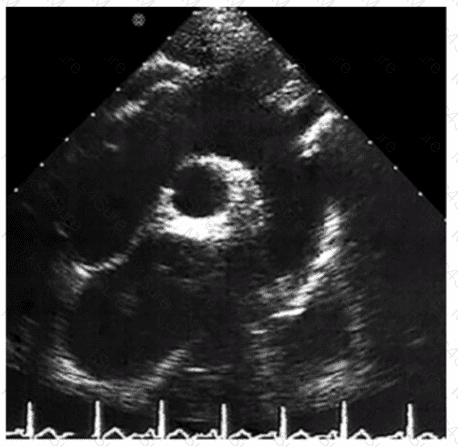

Which is the most likely abnormality represented in these images from a 48-year-old man with shortness of breath?